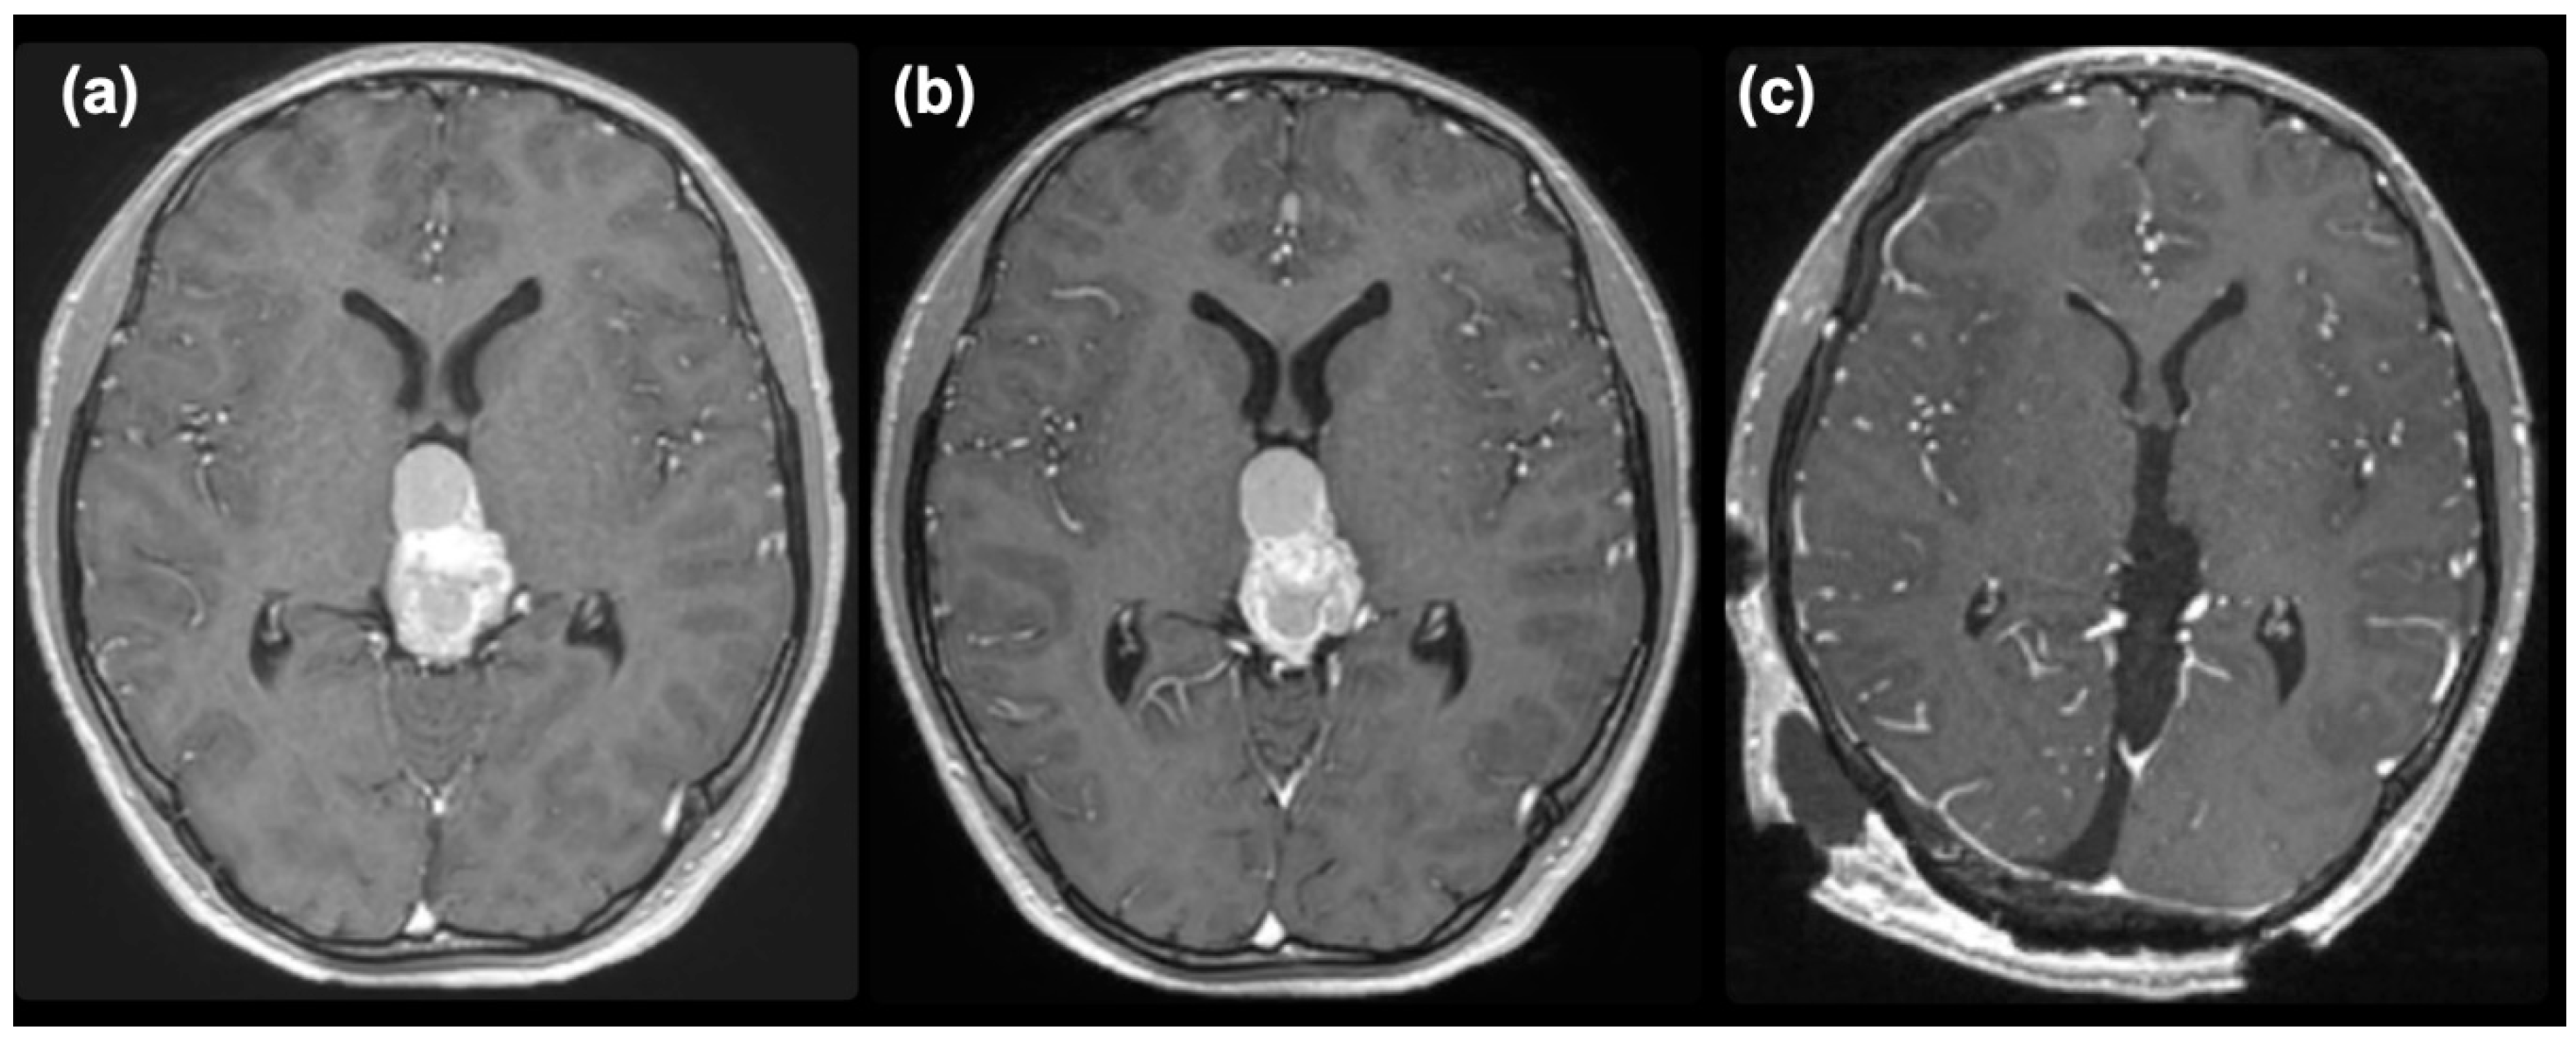

The mixed germ cell tumor was determined to be of intermediate risk according to the Matsutani classification [2,3], and a chemotherapeutic regimen followed by irradiation was planned. First, a regimen of carboplatin (450 mg/m2) and etoposide (150 mg/m2 x 3 days) was commenced. An elevation of serum AFP to 81 ng/ml was noted after the commencement of chemotherapy, and enlargement of the tumor and cystic component was observed on MRI (Figure 3(a)). After two courses of chemotherapy, serum AFP had normalized. However, the size of the tumor did not decrease (Figure 3(b)), so we decided to remove the tumor under the suspicion of growing teratoma syndrome. The pineal tumor was completely removed via the occipital transtentorial approach [4] (Figure 3(c)). The recurrent tumor was very hard and was resected en-bloc after the puncture of the cyst.

Figure 3. Post-contrast MR images taken after one course (a), two courses (b) of chemotherapy, and after removal (c).